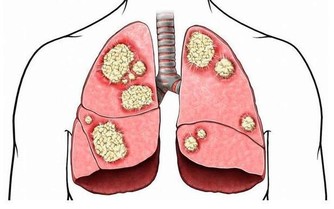

我們就以“燙食”為例,熱乎乎的麵條下肚,穿過胃黏膜,很容易造成胃黏膜收縮甚至破損,為了修復損傷,機體就會在原處繼續生長新的細胞替代,但這個過程並不是十分嚴格,很容易發生錯誤,比如原本應該生長在腸道的細胞過來救急,長在了胃上,這就是化生,是完全錯誤的修補,時間長了,修補面積過多,很容易發展為胃癌。